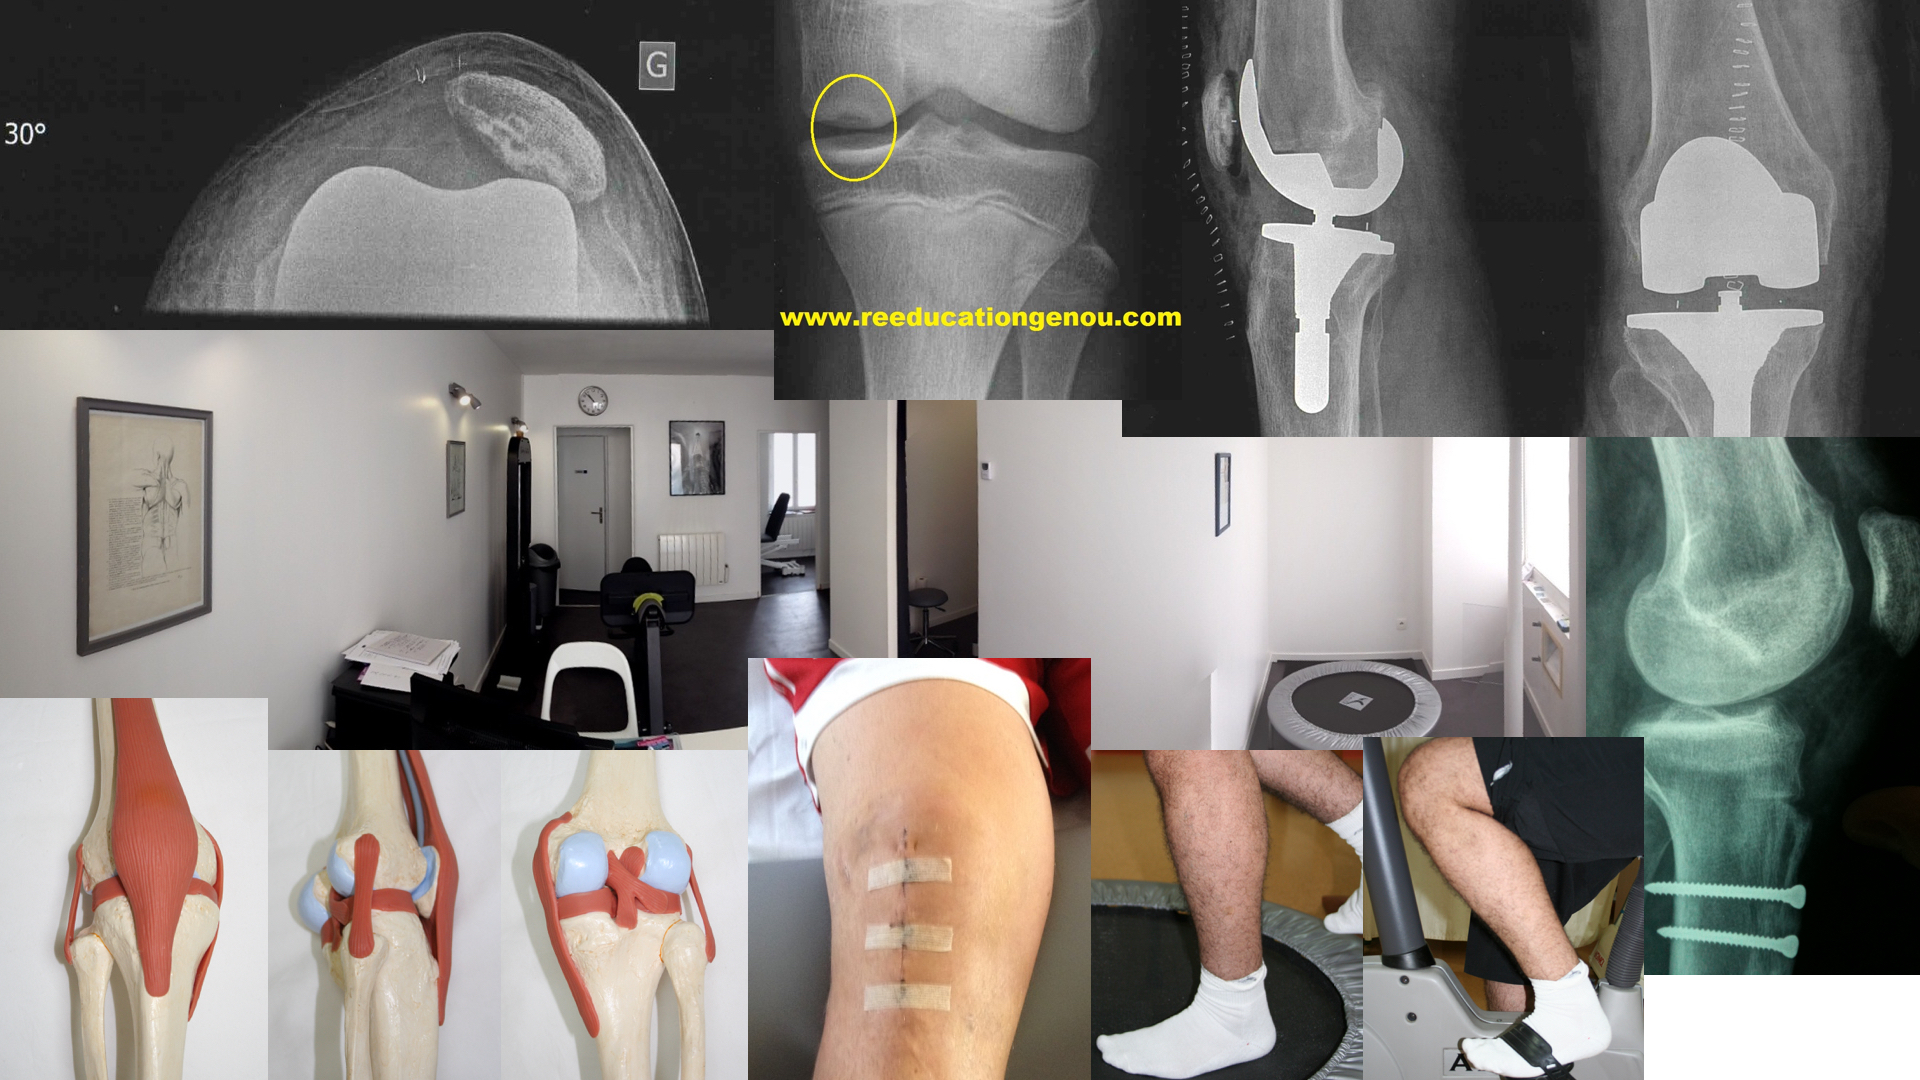

Le matériel minimum du kiné "genou"